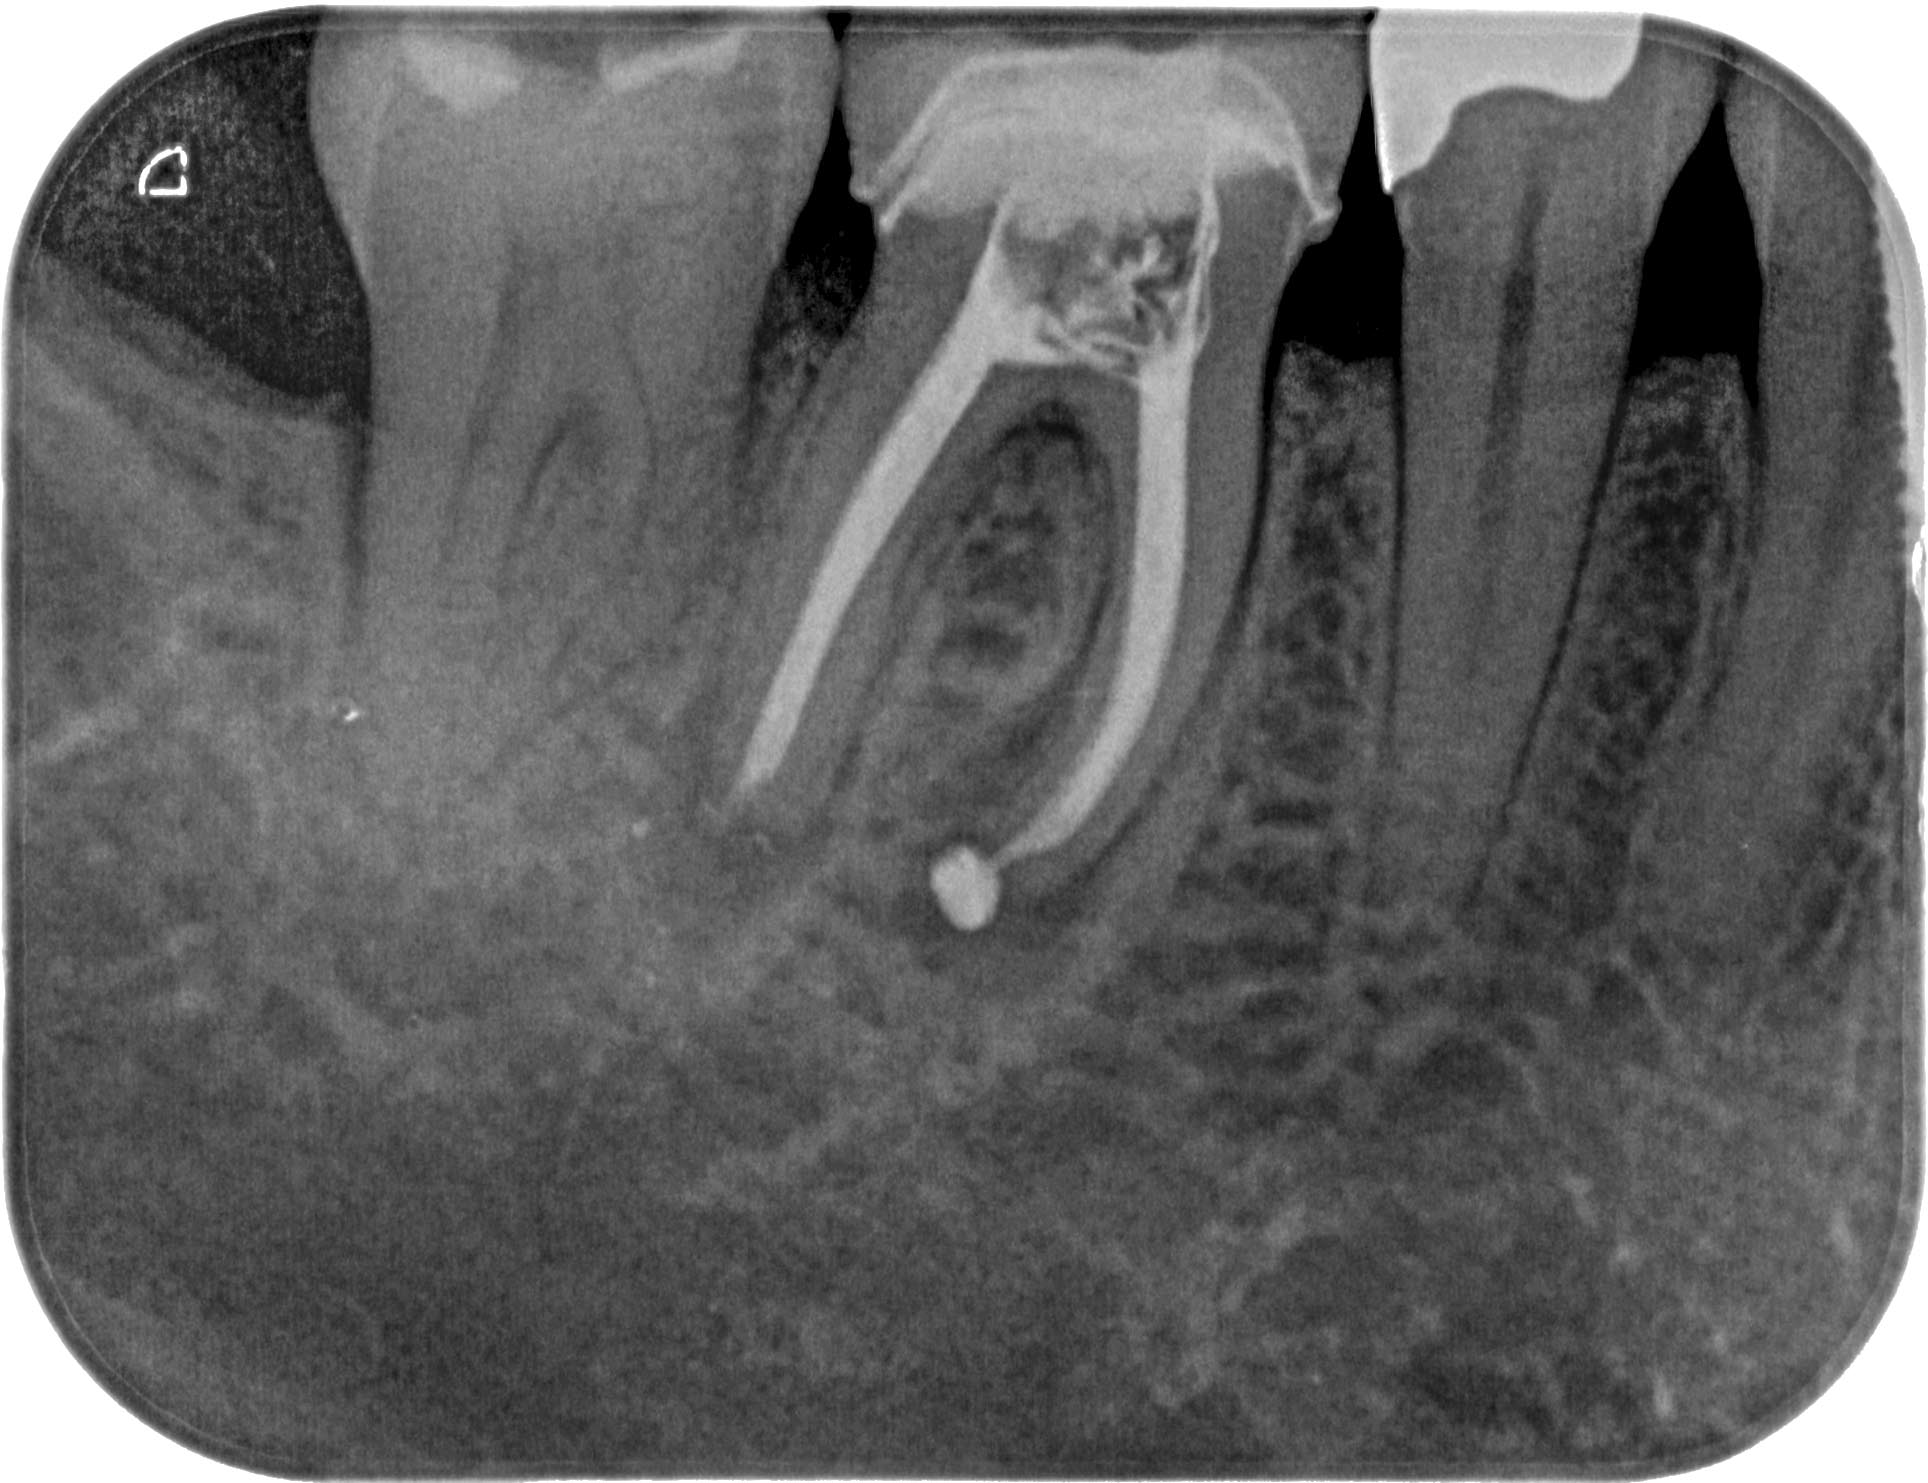

HS46 (2 von 3) Veröffentlicht 21. März 2016 am 1928 × 1483 in Calciumhydroxid- Überpressung (2) 17. November 2015